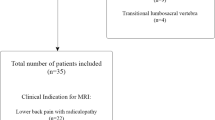

Eighty-five healthy volunteers, with no referred symptoms of lumbar pain, were prospectively recruited from September 2021 to May 2023 and underwent MRI lumbar spine on a 1.5T MR scanner at the Sant'Andrea University Hospital, Rome, Italy. Individuals with incompatible MRI devices, claustrophobic and MRI acquisition with severe motion artifacts were excluded.

From an initial population of 85 healthy volunteers, a total of 80 were included in the study (44 males, 36 females). The participants had a mean age of 42.9 ± 17.1 (range: 21–81) years. Individuals with incompatible MRI devices (n = 1 intrauterine device) and claustrophobic subject who requested the interruption of the scanning (n = 4) were excluded from the study (Fig. 3).